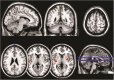

The human brain depends mainly on glucose supply from circulating blood as an energy substrate for its metabolism. Most of the energy produced by glucose catabolism in the brain is used to support intrinsic communication purposes in the absence of goal-directed activity. This intrinsic brain function can be detected with fMRI as synchronized fluctuations of the BOLD signal forming functional networks. Here, we report results from a double-blind, placebo controlled, cross-over study addressing changes in intrinsic brain activity in the context of very low, yet physiological, blood glucose levels after overnight fasting. Comparison of four major resting state networks in a fasting state and a state of elevated blood glucose levels after glucagon infusion revealed altered patterns of functional connectivity only in a small region of the posterior default mode network, while the rest of the networks appeared unaffected. Furthermore, low blood glucose was associated with changes in the right frontoparietal network after cognitive effort. Our results suggest that fasting has only limited impact on intrinsic brain activity, while a detrimental impact on a network related to attention is only observable following cognitive effort, which is in line with ego depletion and its reliance on glucose.